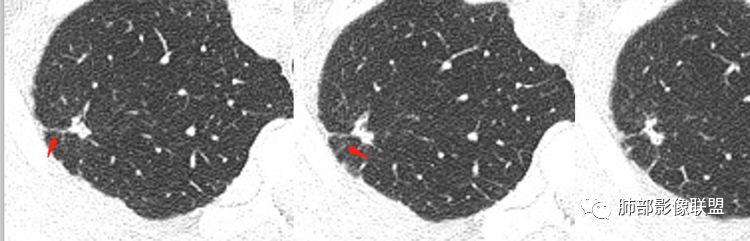

2.右肺上叶胸膜下不规则实性密度小结节影,密度均匀。边界清楚,缺乏典型深分叶,除个别层面上圆隆外,大多边缘平直甚至内凹,成三角形轮廓,冠状位甚至状如“奔驰”车标。

3.可见棘状突起或条索影牵于胸膜间,胸膜侧可见毛刺。灶周未见磨玻璃影。

4.周围肺组织见小结节影,胸膜多见结节样增厚。

相邻胸膜增厚——周围肺组织小结节影,肺尖胸膜结节样增厚,范围较广,支持慢性病灶。